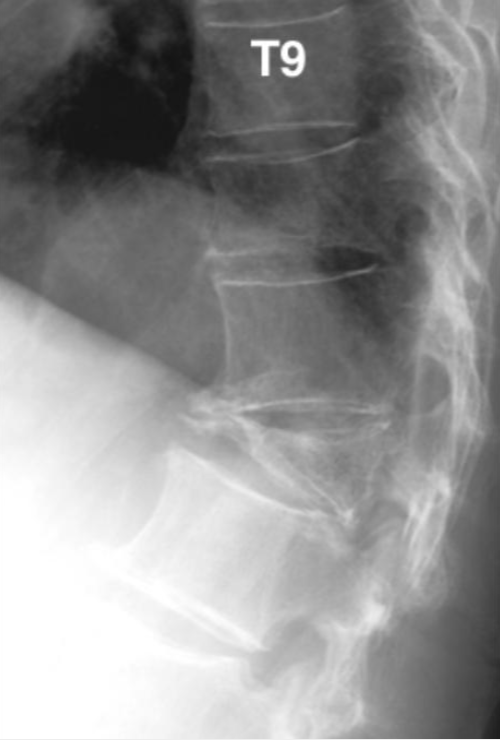

Anterior wedging: the classic finding, where the front of the vertebral body collapses while the back remains relatively intact, resulting in a wedge-shaped vertebra

≥20% height loss or >4 mm reduction from baseline

Increased radiodensity: the fractured bone often appears whiter on the X-ray due to compaction of trabecular bone

Cortical step-off: disruption in the normal smooth, rectangular outline of the vertebra

Kyphotic deformity: severe cases or multiple fractures can cause the spine to curve forward, creating a “round back” or “dowager’s hump” (4,5).

Kümmell disease involving the T10 vertebral body with an osteoporotic spinal compression fracture at T12 - wedge shape deformity (5).